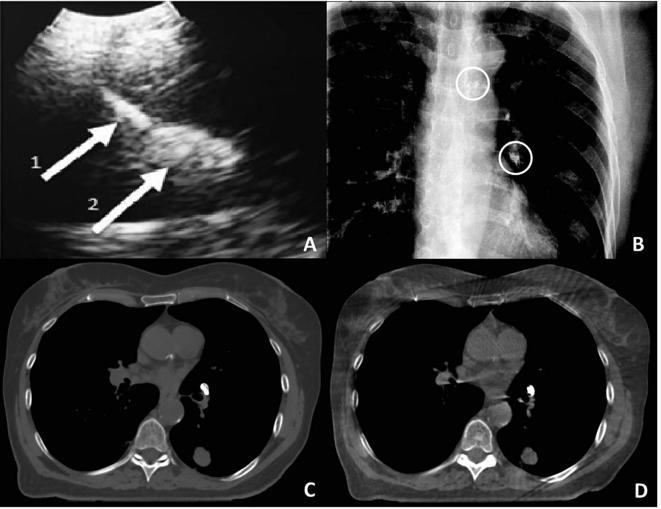

Safety and clinical feasibility of injecting a novel liquid fiducial marker for use in image guided radiotherapy in 15 patients with non-small cell lung cancer are reported. No major safety or toxicity issues were encountered. Markers present at start of radiotherapy remained visible in cone beam computed tomography and fluoroscopy images throughout the treatment course and on computed tomography images during follow-up (0-38 months). Marker volume reduction was seen until 9 months after treatment, after which no further marker breakdown was found. No post-treatment migration or marker related complications were found.

报告了15例非小细胞肺癌患者注射一种用于图像引导放射治疗的新型液体基准标记物的安全性和临床可行性。未遇到重大安全或毒性问题。放疗开始时存在的标记物在整个治疗过程中的锥束计算机断层扫描和荧光透视图像中以及随访期间(0 - 38个月)的计算机断层扫描图像中均可见。治疗后9个月前可见标记物体积减小,此后未发现标记物进一步分解。未发现治疗后迁移或与标记物相关的并发症。